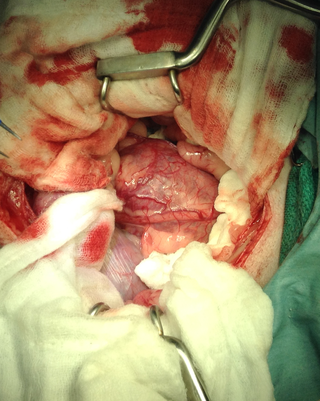

右心耳に発生する血管肉腫では右肋間開胸術(状況により正中切開術)により、心拍動下で心タンポナーデをおこしている心臓にアプローチ。

腫瘍化した右心耳にサチンスキーで腫瘍基部と右心房の間隙をクランプする。牽引後、TA30Vを挿入しステープリングを行う。

※腫瘍化した右心耳にアプローチしている所。術後には抗癌剤治療が行われます。